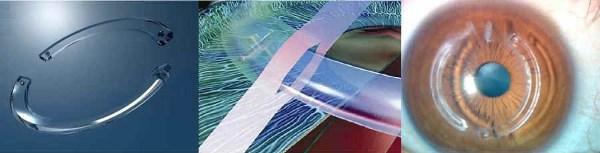

– Anel intraestromal

O anel intraestromal é um pequeno implante semicircular inserido no interior da córnea. Sua função é regularizar a curvatura corneana. Sendo assim, ele não interrompe a progressão da doença, mas melhora a geometria da córnea e, com isso, a qualidade visual.

Diferente do crosslinking, que busca estabilizar a doença, o anel é um tratamento voltado à reabilitação visual. Ele pode permitir, inclusive, o uso de óculos ou lentes gelatinosas em casos em que antes só era possível o uso de lentes rígidas ou esclerais.

O procedimento é minimamente invasivo e, na maioria dos casos, realizado com o laser de femtosegundo e o retorno visual ocorre geralmente em poucos dias.

Pós-operatório do Anel intraestromal

O pós-operatório do implante de anel é, em geral, tranquilo. A visão pode flutuar nos primeiros dias, mas tende a melhorar gradualmente. O retorno às atividades costuma acontecer em poucos dias, com restrições específicas que explico detalhadamente a cada paciente. O uso de colírios e o controle rigoroso da resposta inflamatória são fundamentais para o sucesso do procedimento.